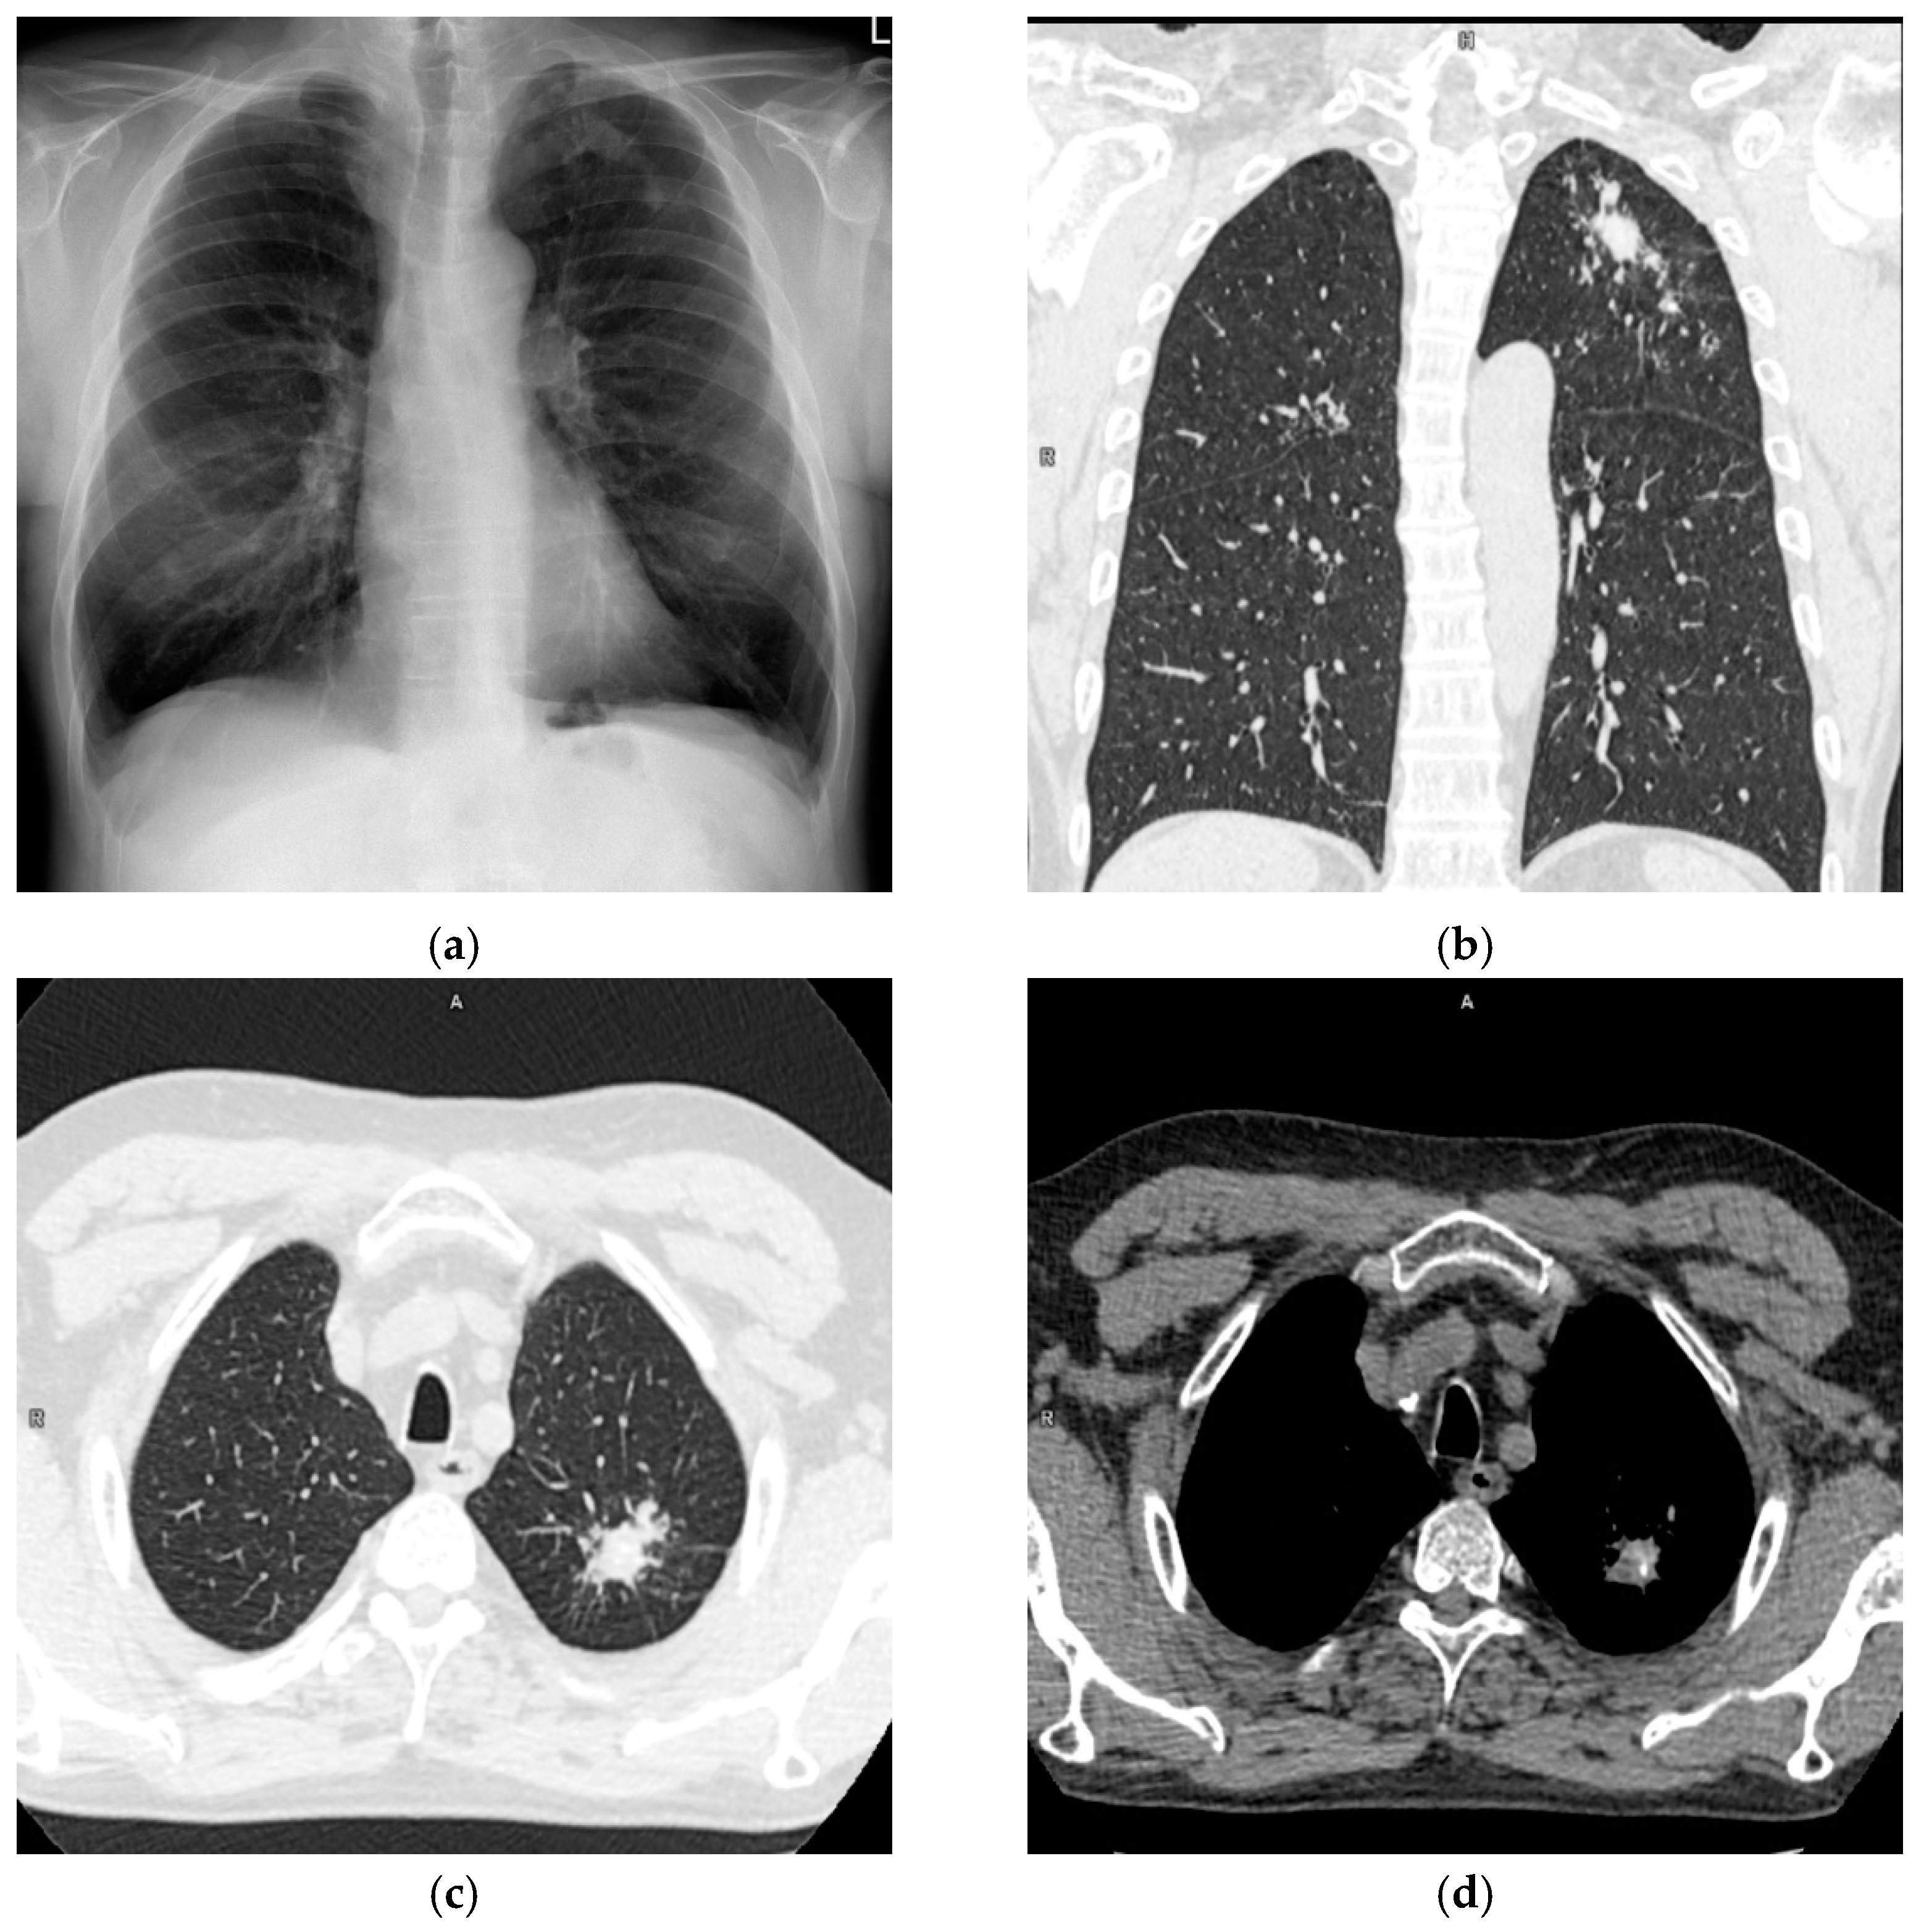

A 62-year-old male was admitted to the Department of Thoracic Surgery of National Tuberculosis and Lung Diseases Research Institute due to a focal lesion localized in the left lung. Irregular shape consolidation in the upper zone of the left lung was found in a chest X-ray (Figure 1a). Chest CT (chest computed tomography) revealed several nodules of various shapes and sizes, with small calcifications, localized in the apicoposterior segment of the left lung. The largest nodule, measuring 28 × 23 mm, had spiculated borders (Figure 1b–d). These findings were ambiguous, requiring differentiation between tuberculosis and neoplasm.

Figure 1.

Chest X-ray and CT (a). Chest X-ray, posteroanterior projection. Irregular shape consolidation in the upper zone of the left lung. (b). Chest CT, lung window, coronal image. Various shape and size lung nodules in the left upper lobe. (c) Chest CT, lung window, axial image. The largest lung nodule with spiculated borders is in the left upper lobe. (d) Chest CT, mediastinal window, axial image. Calcifications in lung nodules.